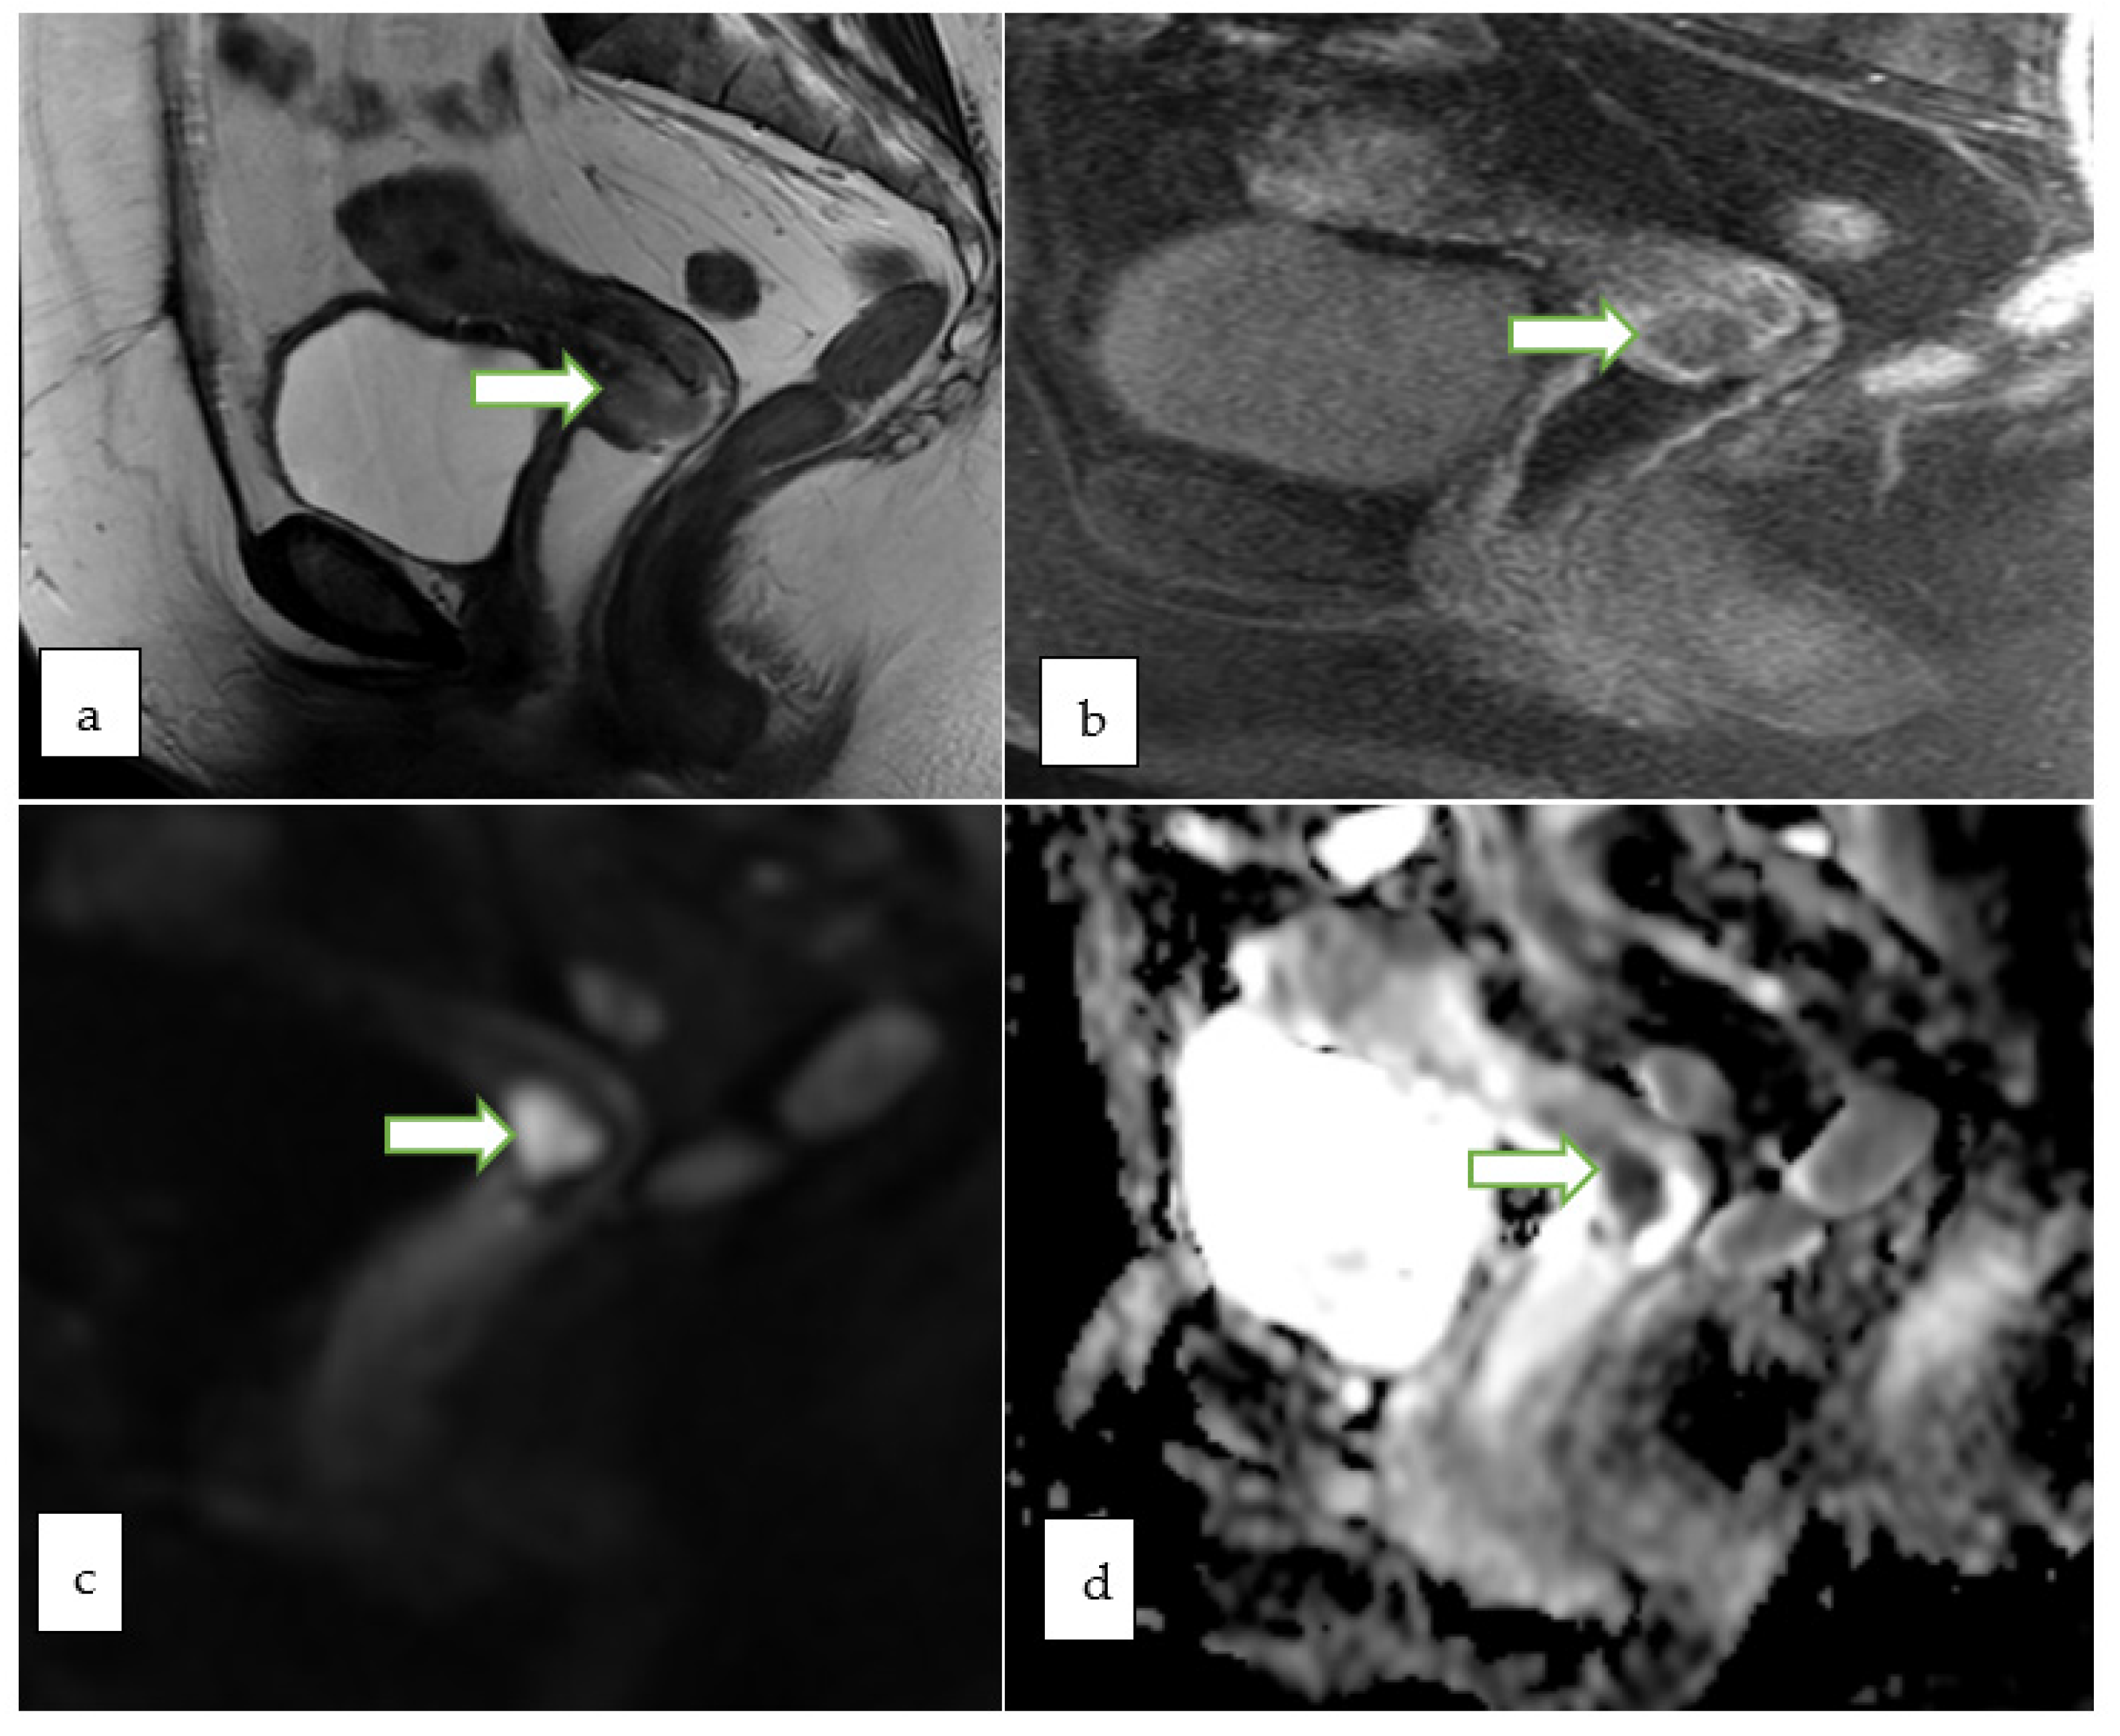

4.2. Magnetic Resonance Imaging (MRI)

- Nougaret, S.; Lakhman, Y.; Vargas, H.A.; Colombo, P.E.; Fujii, S.; Reinhold, C.; Sala, E. From Staging to Prognostication: Achievements and Challenges of MR Imaging in the Assessment of Endometrial Cancer. Magn. Reson. Imaging Clin. N. Am. 2017, 25, 611–633. [Google Scholar] [CrossRef]

- Otero-García, M.M.; Mesa-Álvarez, A.; Nikolic, O.; Blanco-Lobato, P.; Basta-Nikolic, M.; de Llano-Ortega, R.M.; Paredes-Velázquez, L. Role of MRI in staging and follow-up of endometrial and cervical cancer: Pitfalls and mimickers. Insights Imaging 2019, 10, 19. [Google Scholar] [CrossRef]